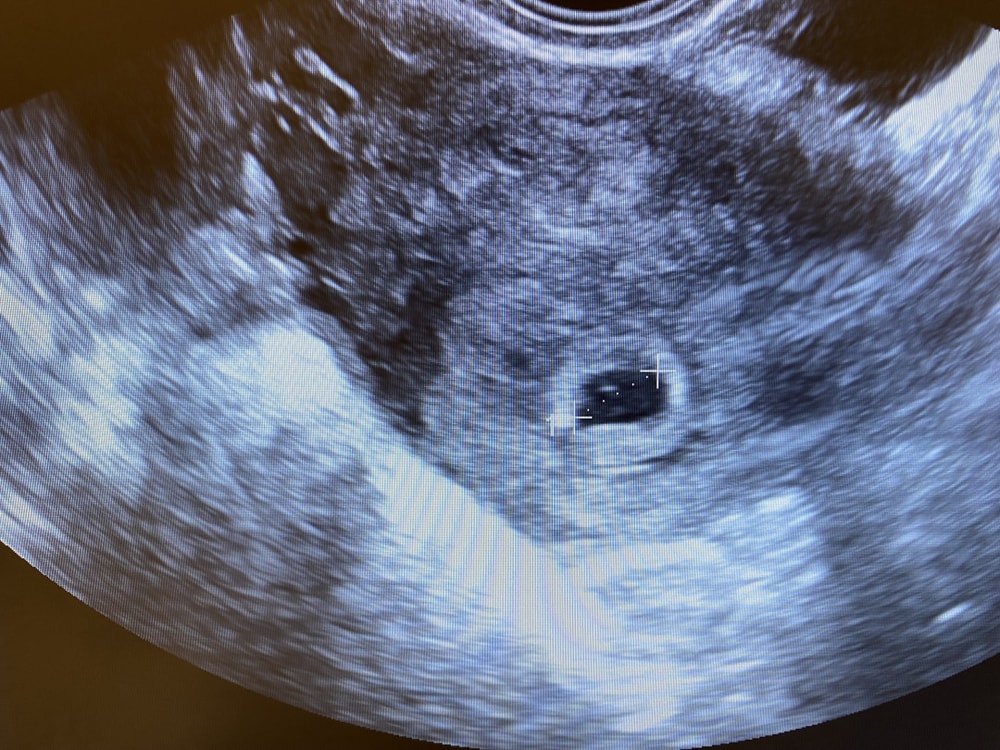

УЗИВсем доброе утро, вопрос такой можно ли с такими тестами сходить уже завтра на узи? Покажет плодное яйцо или подождать ещё неделю?

Акушерский срок по подсчетам 4-5 недель, 14-15 ДПО сегодня)

Я ходила в 4нед6дней по месячным. 21-22ДПО. В матке увидели такой кругляшок в домике

Единорожка, да зачем? Просто подождите 2 недели. Врачи не рекомендуют ранние УЗИ. А дырявить вену тоже не надо. И так все понятно. Завтра на УЗИ не увидят ничего. Через неделю увидят маленькое плодное яйцо. Через 2 недели на сроке 6+ эмбрион, ещё чуть позже - сердцебиение (пульсацию). Так что лучше пока не лазить туда, там самые тончайшие процессы закладки органов происходят